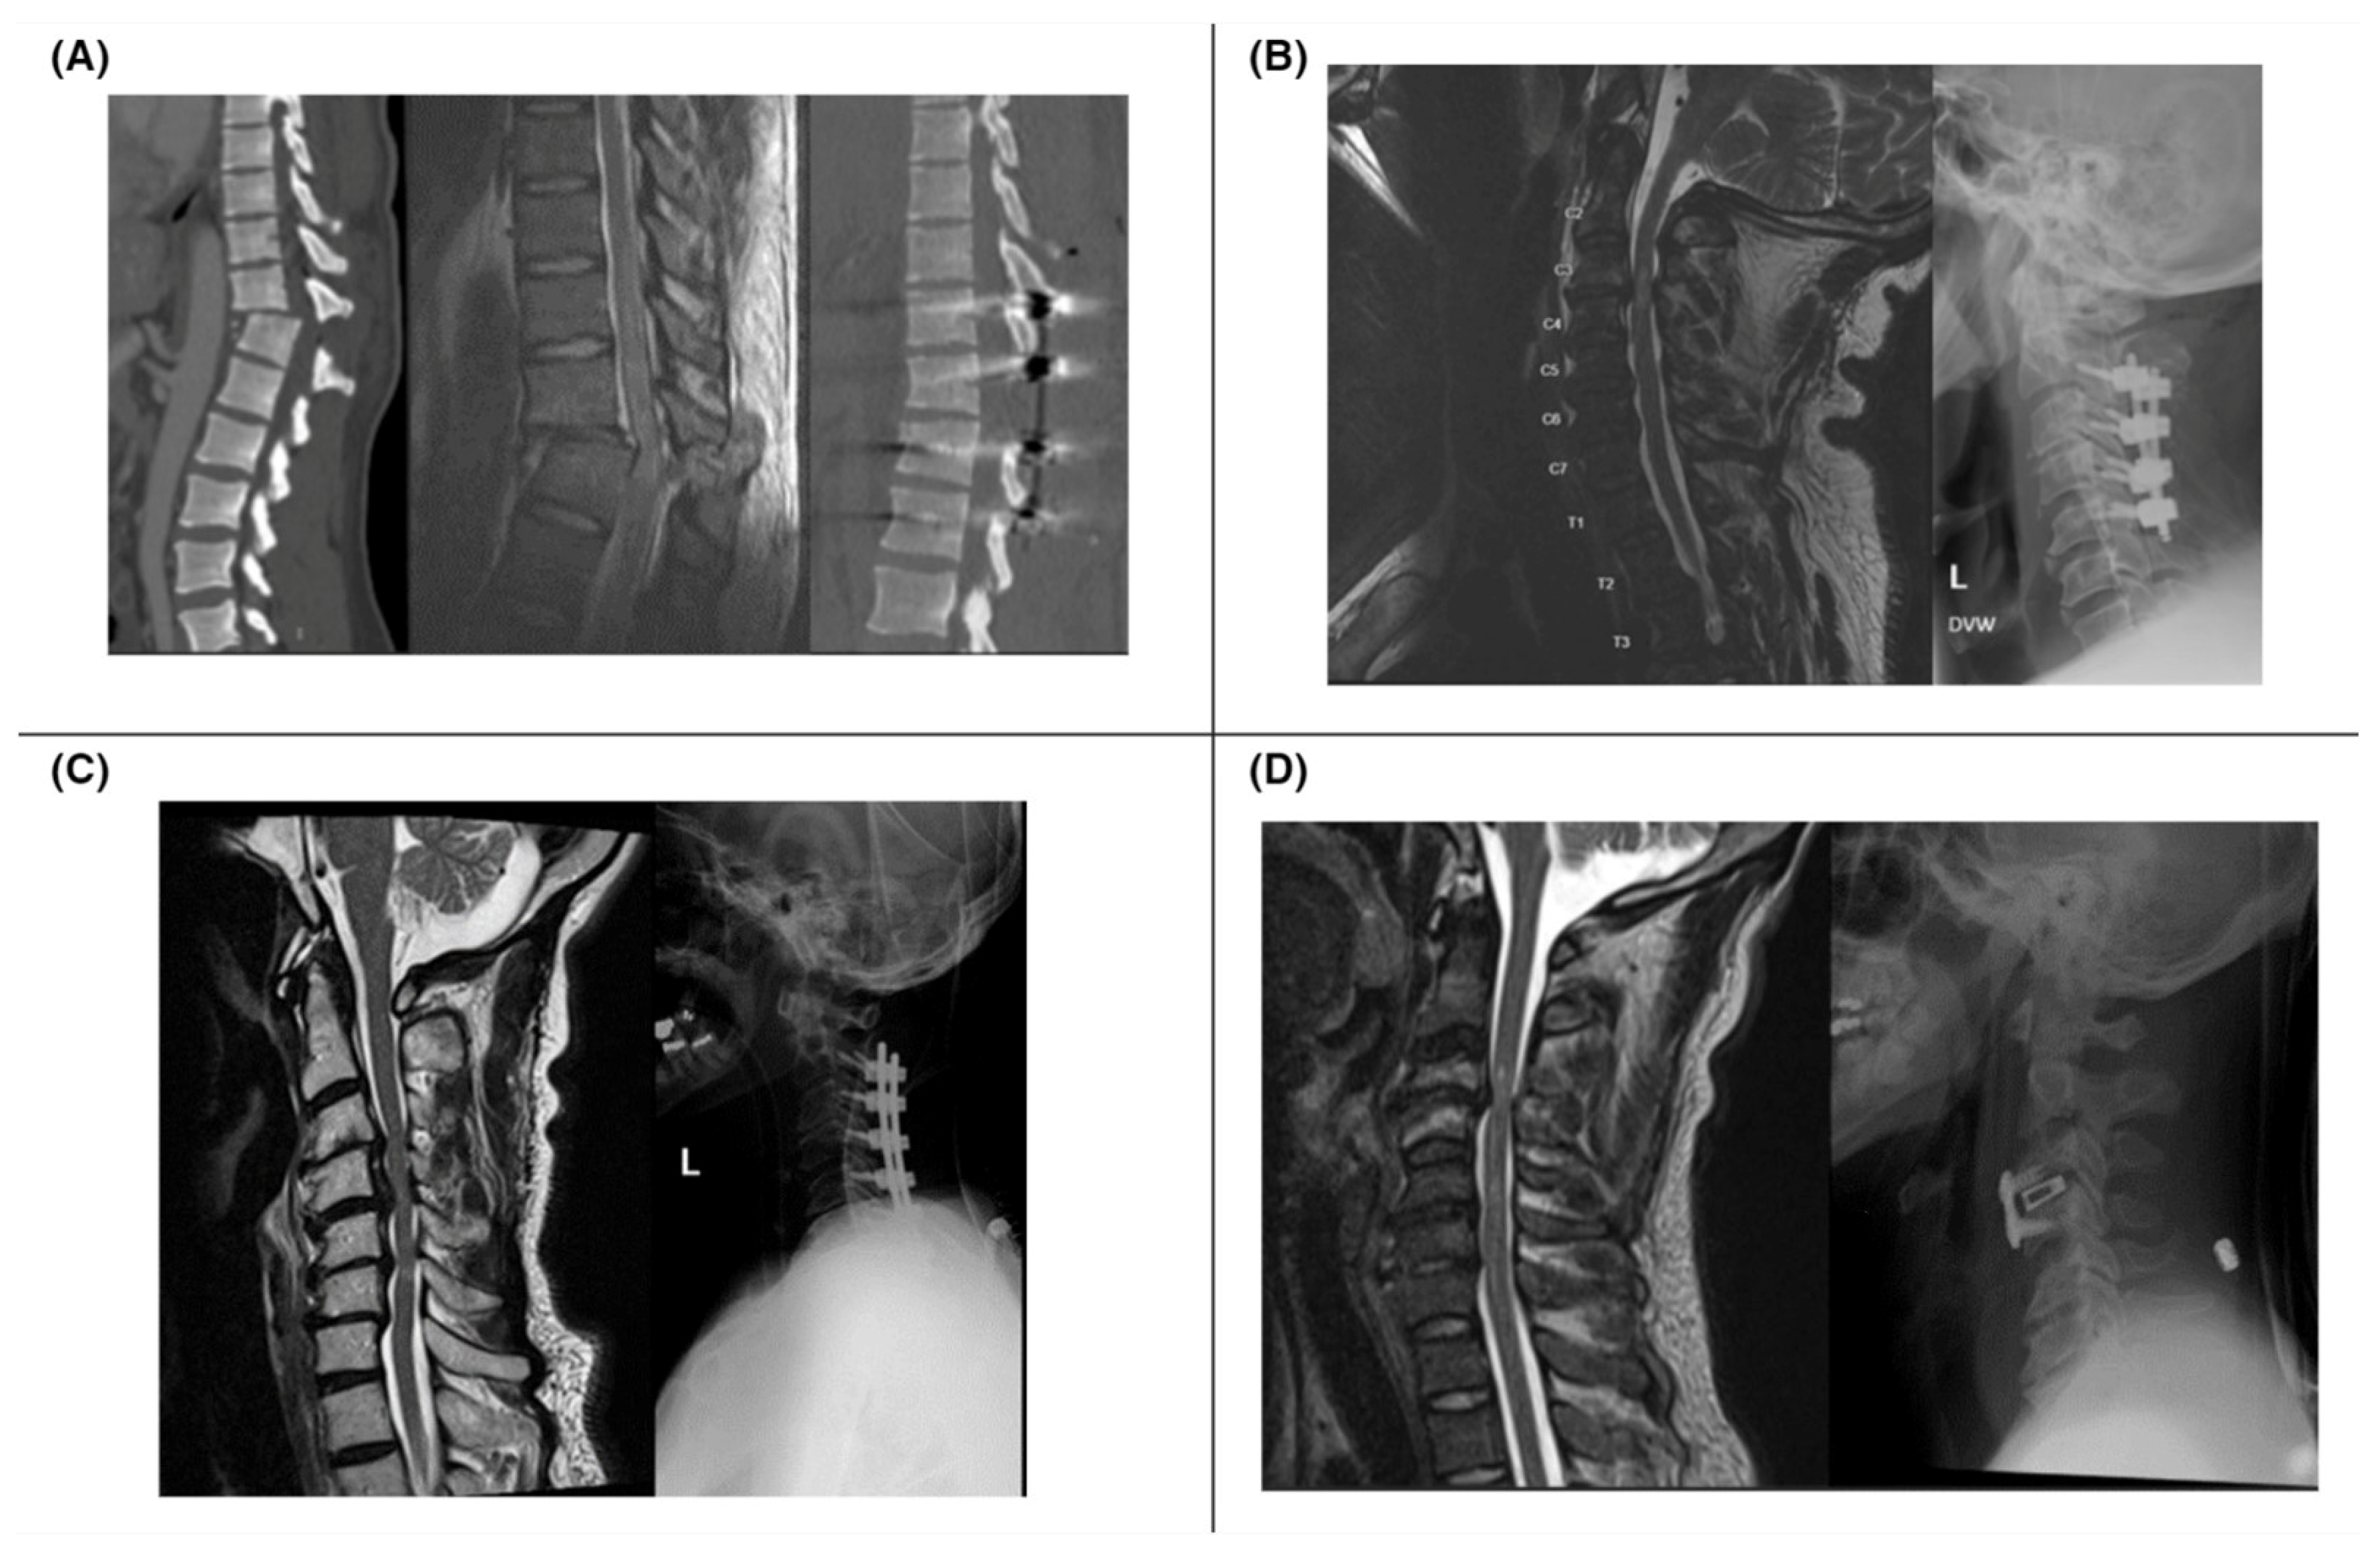

A complete SCI is characterized by the loss of both sensory and motor functions below the neurologic level of injury (NLI), while an incomplete injury involves preservation of either sensory or motor function below the level of injury [9]. Based on these assessments, an AIS grade (A–E) is assigned (Table 3) to classify the severity of the injury. Figure 1 provides examples of pre- and post-operative imaging of SCI patients with varying AIS grades.

Figure 1.

(A) Patient with lower extremity motor and sensory loss after MVC (ASIA A); CT (left) and sagittal T2 MRI (middle) show T11–12 fracture dislocation; postoperative CT shows improved alignment (right). (B) Patient with intact sensation but no motor function after fall (ASIA B); preoperative MRI (left) shows C3–4 stenoses and cord contusion; postoperative decompression and fusion from C2–5 X-ray (right). (C) Patient with 2/5 hand weakness and intact sensation (ASIA C) after fall; MRI with spinal cord contusion at C4–6 (left); postoperative X-ray with instrumented decompression and fusion (right). (D) Patient with hand paresthesia and intact motor function after fall (ASIA D); MRI with traumatic disc herniation at C3–4 (left); postoperative C3–4 anterior cervical discectomy and fusion X-ray (right).